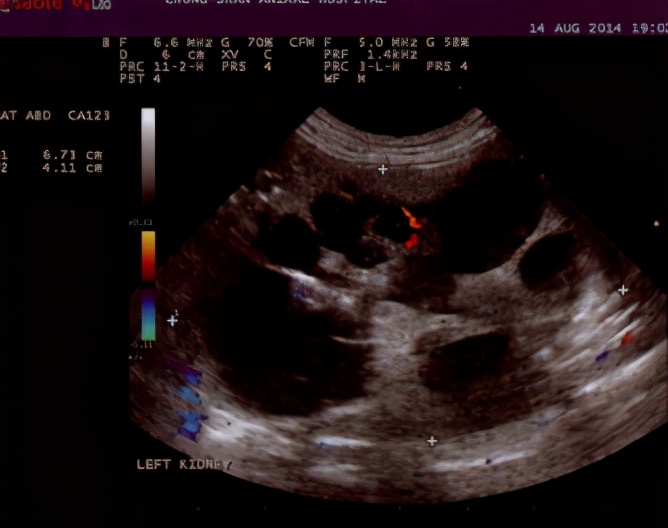

主要通过腹部B超确诊。大多病例也是在腹部B超体检时发现的。患病猫最快在4周龄就可以通过B超扫描到多囊肾,但此时没有发现囊肿不代表在年龄更大时不会形成囊肿,在10月龄后确诊的准确率高达95%。如果多囊肾没有影响到肾脏外形时,X光检查并不能看出来。